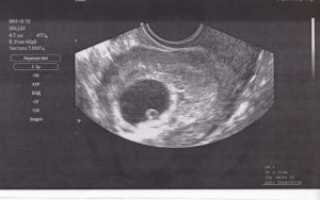

Во время первого ультразвука специалист-диагност выявляет образование с повышенной эхогенностью. Так выглядит плодное яйцо, величина которого позволяет судить о сроке данной беременности.

Ещё на мониторе будут видны желточный мешок, расположение зародыша, толщина внутреннего слоя матки. Врачи убедятся в отсутствии у женщины воспалений, полипов, кист и опухолей. Расшифровывать данные должен только профильный диагност.

Во время первого УЗИ обнаруживаются:

- круглое или каплевидное образование с низкой эхогенностью размером 3-5 мм. Его размер определяет срок;

- тонкая оболочка вокруг развивающегося ребёнка;

- жёлтое тело – оно вырабатывает прогестерон, способствующий сохранению плода.